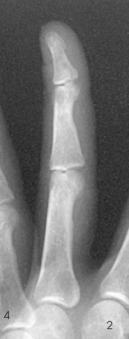

Structures shown: A PA projection of the appropriate digit is visualized (Figs. 4-16 through 4-19).

Structures shown: A lateral projection of the affected digit is shown (Figs. 4-24 through 4-27).

Structures shown: The resultant image shows a PA oblique projection of the bones and soft tissue of the affected digit (Figs. 4-32 through 4-35).